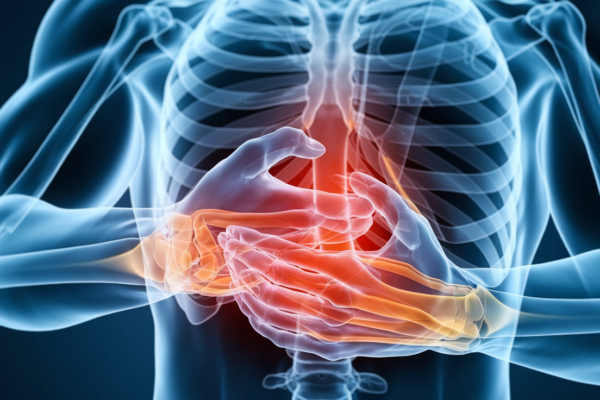

Chest Pain After Eating: Causes, Symptoms & Fast Relief

Chest pain after eating, or postprandial chest discomfort, affects up to 15% of adults and typically causes a burning, squeezing...

Chest pain after eating, or postprandial chest discomfort, affects up to 15% of adults and typically causes a burning, squeezing...